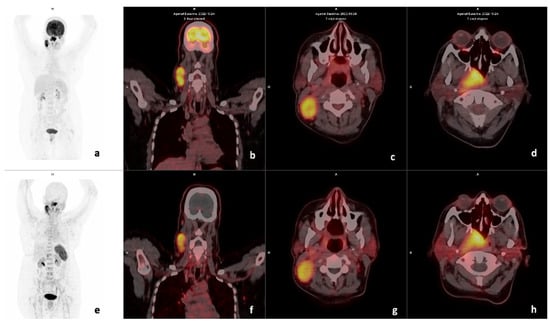

3.3. Visual Analysis